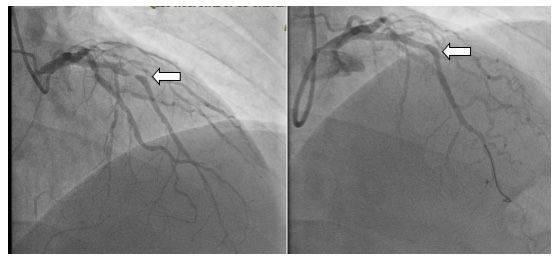

術(shù)前(左側(cè)圖)與生物可吸收支架術(shù)后(右側(cè)圖)血管血流對比圖

首先應用藥物球囊開通了完全閉塞的右冠狀動脈,隨后成功應用藥物球囊解除了回旋支的嚴重狹窄,最后在前降支嚴重狹窄處成功植入生物可降解支架1枚,手術(shù)過程順利。術(shù)后,患者三支主要的冠狀動脈均順利完成再灌注治療,血管狹窄完全解除,患者癥狀明顯緩解。